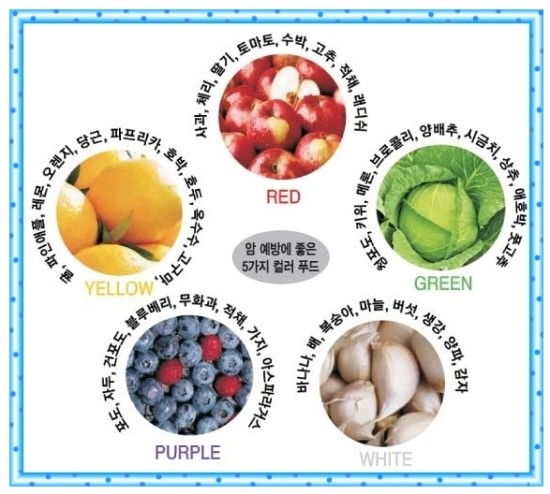

한때 미국 등 서구에서나 발병하는 질환으로 알던 대장암이 우리도 선진국으로 진입하고 식습관은 곡류에서 육류로 급속히 패턴이 바뀌면서 대장질환이 급속히 증가하는 추세이다. 한국중앙암등록본부가 최근 발표한 2011년 국가암등록사업 자료에 의하면 2009년 1년 동안 새롭게 암으로 진단받은 암발생자는 19만2561명 (남 9만9224명, 여 9만3337명)으로 2008년도 18만465명에 비해 6.7% 늘었다. 세계보건기구(WHO) 산호 국제암연구소가 세계 184개국을 대상으로 조사한 세계 대장암 발병현황에 따르면 한국 남성의 대장암 발병률은 10만 명당 46.92명으로 슬로바키아(60.62명), 헝가리(56.39), 체코(54.39)에 이어 세계 4위, 아시아국 1위를 차지했고,여성의 경우도 10만 명당 25.64명으로 젠 세계 184개국 중 19번째를 차지하였다. 암종별로 남자는 위암, 대장암, 폐암, 간암 순이었고, 여자는 갑상선암, 유방암, 대장암, 위암 순으로 많이 발생했으며, 여성에서 처음으로 대장암이 위암을 앞질렀다. 이 때문에 40대 이상이라면 정기적으로 내시경 검사를 받는 것이 좋다. 대장암의 원인 대장암은 음식문화와 생활습관이 직접적으로 연관되는 대표적인 암이다. 과거에 비해 발생률이 증가한 가장 큰 이유는 식습관의 변화 즉, 식생활의 서구화다. 식물성 섬유소 섭취는 감소하고 동물성지방과 단백질 섭취는 증가하는 육류 위주의 식생활이 문제다. 육류와 햄버거, 감자튀김 등 인스턴트 식품 섭취 증가가 주원인으로 꼽힌다. 더 구체적으로 표현하면 과다한 육류 섭취 및 고지방식 때문이다. 동물성 지방을 많이 섭취하면 간에서 콜레스테롤과 담즙산의 분비가 증가된다. 콜레스테롤은 대사 과정에서 발암물질을 만들며, 담즙산은 대장 세포를 손상시킨다. 섬유질 섭취가 부족한 것도 문제다. 섬유질은 음식물이 장을 통과하는 시간을 단축시킴으로써 발암물질과 장 점막과의 접촉시간을 단축시키고 장 내 발암물질을 희석시키는 작용을 한다. 또한 스트레스 및 불규칙한 생활 습관, 과도한 음주, 흡연도 대장암의 원인이라 할 수 있다. 유전적인 요인도 존재하며, 대장암은 약 10~30%의 환자에게서 가족력을 보인다고 알려져 있다. 대표적으로 스트레스 많이 받는 직장인이 흡연과 함께 잦은 술자리에서 삼겹살에 소주를 마신다면 위험인자에 전면적으로 노출되고 있는 샘이다. 대장용종이란 대장 점막이 비정상적으로 자라 조그만 혹같이 돌출되어 있는 상태를 말한다. 50세 이상인 경우 30-40% 가량에서 대장용종이 발견되고 있으며 대부분 내시경적으로 절제가 가능하다. 조기대장암 치료-내시경적 절제술 한국의 대장암 치료성적은 세계 1위 수준이다. 우리나라 대장암 5년 생존율은 지난 15년 동안 54.8%에서 70.1%로 크게 향상됐다. 이는 미국 65%, 캐나다 61%, 일본 65% 등 의료 선진국보다 훨씬 높은 수치다. 내시경검사를 통한 조기발견과 치료기술이 발달한 결과다. 내시경검사를 하면 마치 장속에 들어가서 직접 눈으로 보는 것 같은 선명한 영상을 얻을 수 있다. 그리고 검사하는 동안 병변이 있으면 즉시 떼어내서 조직검사를 할 수 있다. 병변이 작은 경우는 한 번에 모두 제거할 수도 있다. 만일 종양이 발견되면 조직검사를 통해 현미경으로 진단한다. 점막에 국한된 조기 대장암의 경우에는 내시경적 절제술로 치료가 가능하다. 그러나 내시경적 절제술 후 떼어낸 조직을 면밀히 검토했을 때 일부 추가수술이 필요할 수도 있다. 대장암 치료에 있어 수술적 치료는 가장 근본이 되는 치료이다. 과거에는 20cm의 절개창을 내는 개복술이 주를 이루었으나, 최근에는 복강경을 이용한 수술이 많이 이루어지고 있는 추세이다.

대장암에 안 걸리려면 편식을 하지 않고 음식을 골고루 섭취해야 하며 육류나 패스트푸드보다는 신선한 채소와 과일이 몸에 좋다. 하루 30분 이상 규칙적인 운동을 해야하며 적정한 체중을 유지해야 한다. 모든 병의 근원인 담배를 끊고 과음도 피해야한다. 무엇보다도 정기검진을 통해 용종을 발견하고 제거하는 것이 가장 효과적인 예방법이라고 전문의들은 입을 모은다. 경기도 안산 한사랑병원 최동현 원장은 “대장암의 원인은 환경적 요인과 유전적 요인이 복합되어 발생한다고 알려져 있는데, 대장암 가족력이 있을 경우 그렇지 않은 사람에 비해 대장암 발병율이 2~3배 정도 높다고 알려져 있으므로 신경써서 정기적인 검사를 해보시는 것이 좋다”며 “대장암의 대부분은 선종성 용종에서 비롯된다고 알려져 있기 때문에 조기에 발견하여 제거해버린다면 대장암의 상당부분은 예방할 수 있으므로 40대 이상 중장년층은 정기적으로 내시경검사를 받아야한다”고 조언했다. 유로저널 김태호 기자 eurojournal02@eknews.net